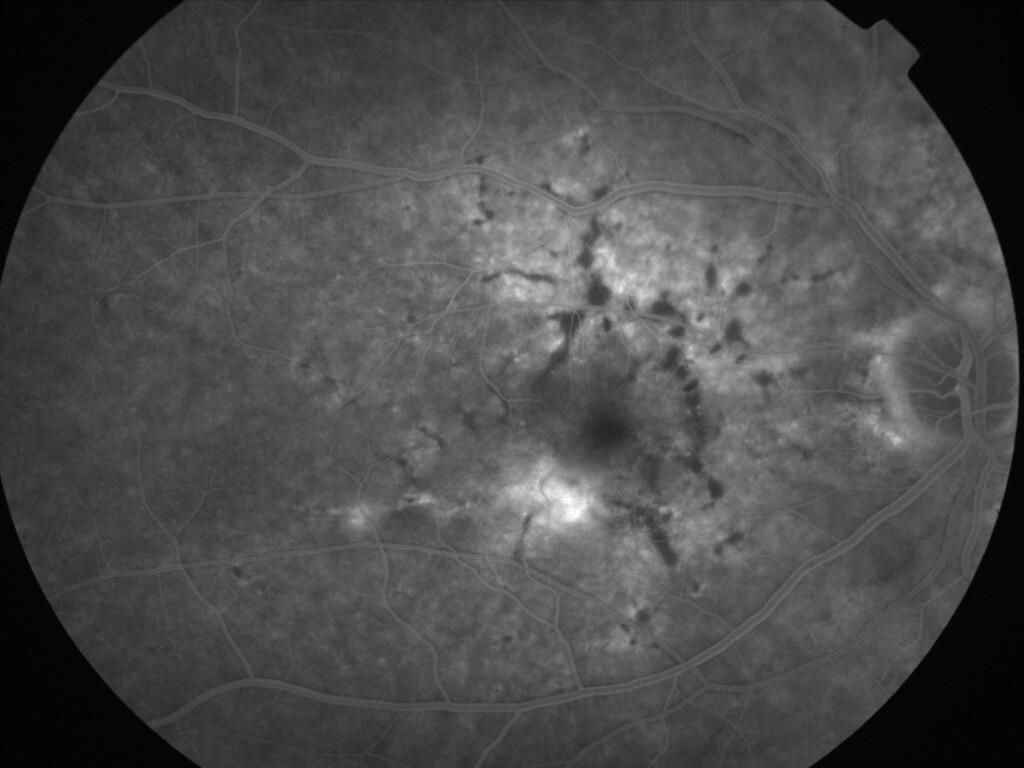

ASSOCIATION STRIES ANGIOIDES ET DYSROPHIE MACULAIRE RETICULEE

NEOVASCULARISATION